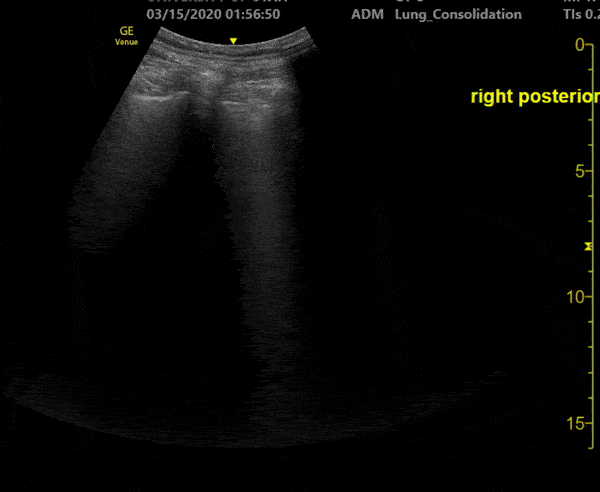

This is an ultrasound clip of the right posterior lung field of a patient with confirmed COVID-19 pneumonia. The patient presented to the emergency department on day 3 of symptoms with fever. They were found to be tachypneic and with mild hypoxia. [Clip 3/3] Lung ultrasound demonstrates confluent B lines associated with a small subpleural consolidation. Image courtesy of Fritz Fuller (@POCUS_Society)